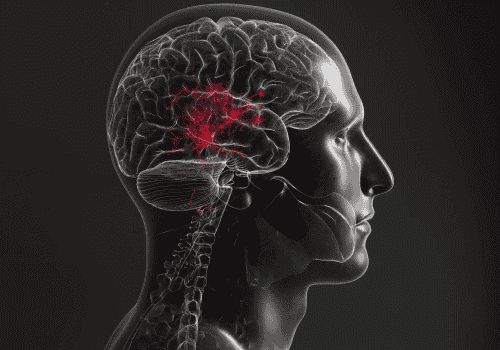

كشفت دراسة حديثة أجراها باحثون من جامعتي ساو باولو البرازيلية وأوكلاند النيوزيلندية عن أدلة جديدة تشير إلى أن منطقة محددة في الدماغ قد تلعب دورا مباشرا في بعض حالات ارتفاع ضغط الدم.

وأوضحت الدراسة أن المنطقة الدماغية الجانبية المجاورة للوجه (pFL) قادرة على إحداث تغيّرات بيولوجية تؤدي إلى رفع ضغط الدم، وهي منطقة ترتبط بالتحكم في التنفس، لا سيما الزفير القوي والمتعمّد أثناء ممارسة الرياضة أو السعال أو الضحك.

وأشار الباحثون إلى أن التداخل بين تنظيم التنفس وإشارات الأوعية الدموية قد يفسّر استمرار ارتفاع ضغط الدم لدى نسبة تصل إلى نحو 40 بالمئة من المرضى، رغم استخدام الأدوية الخافضة للضغط.

واعتمد الفريق البحثي على تقنيات الهندسة الوراثية لتنشيط أو تثبيط هذه الخلايا، مع مراقبة تأثير ذلك على النشاط العصبي المرتبط بالتنفس وضغط الدم، حيث أدى تنشيطها لدى بعض الفئران إلى تحفيز مسارات دماغية انتهت بارتفاع ضغط الدم.

كما تمكن الباحثون من رسم خريطة تفصيلية لنشاط جذع الدماغ والأعصاب، ما يفتح المجال أمام مسارات علاجية جديدة تستهدف هذه المنطقة.

وتسهم هذه النتائج في تفسير زيادة خطر الإصابة بارتفاع ضغط الدم لدى الأشخاص الذين يعانون من انقطاع النفس النومي، المرتبط باضطرابات التنفس أثناء النوم.